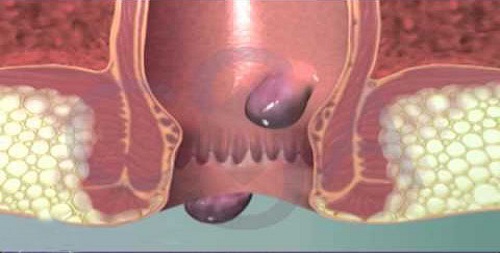

Piles

Piles are collections of tissue and vein that become inflamed and swollen. The size of piles can vary, and they are found inside...